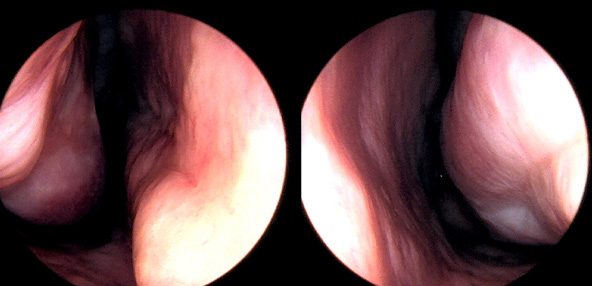

※ 비중격 비염 수술 후 생길 수 있는 부작용으로는 출혈, 감염, 염증이 있을 수 있습니다.

본 사진은 의료기관에서 진료를 본 환자이고, 전후 사진 인물이 동일인이며,동일조건에서 촬영이 되었습니다.